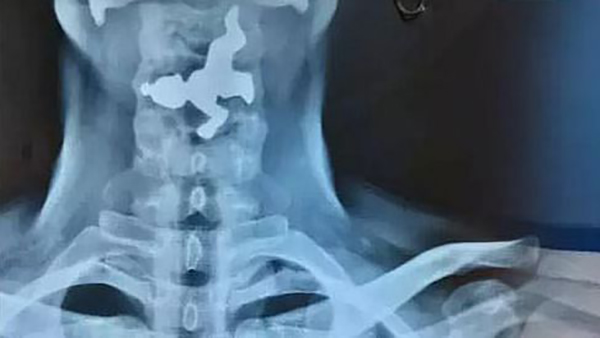

கர்நாடக மாநிலம் பெலகவி மாவட்டத்தில், 45 வயது மிக்க நபர் ஒருவர் தனக்கு தொண்டை வலி இருப்பதோடு மூச்சு விடுவதில் சிரமம் இருப்பதாக கூறி தனியார் மருத்துவமனையை அணுகினார். எனவே அங்குள்ள மருத்துவர்கள் அவருக்கு X-Ray எடுத்து பரிசோதனை செய்தனர். X-Ray ரிப்போர்ட்டை பார்த்த மருத்துவர்கள் அதிர்ச்சியடைந்தனர்.

அதில், அவரது தொண்டையிலுள்ள உணவு குழாயில் இரும்பு வடிவிலான பொருள் ஒன்று சிக்கியுள்ளது தெரிந்தது. பின்னர் இது குறித்து அவரிடம் விசாரித்த போது, தான் எதையும் உட்கோள்ளவில்லை என்று தெரிவித்தார். தொடர்ந்து அவரிடம் கேட்கையில், தான் வழக்கமாக அருகிலிருக்கும் ஒரு கோயிலில் நீராடி, அந்த நீரை பருகுவதாக தெரிவித்தார்.